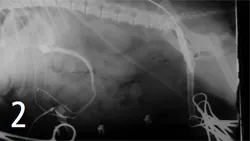

Cystotomy was performed, and mineral composition of these stones was similar to the stones retrieved via the "jiggle technique." Cranial mesenteric arteriography was done to confirm the diagnosis of PSS and to determine whether it was amenable to surgical correction (Figure 2). The portal postcaval shunt was attenuated 75% at the time of surgery, and postattenuation arteriography was performed (Figure 3).

Figure 3. Cranial mesenteric arteriography done after ligation of a PSS reveals no shunting of blood and good intrahepatic arborization.